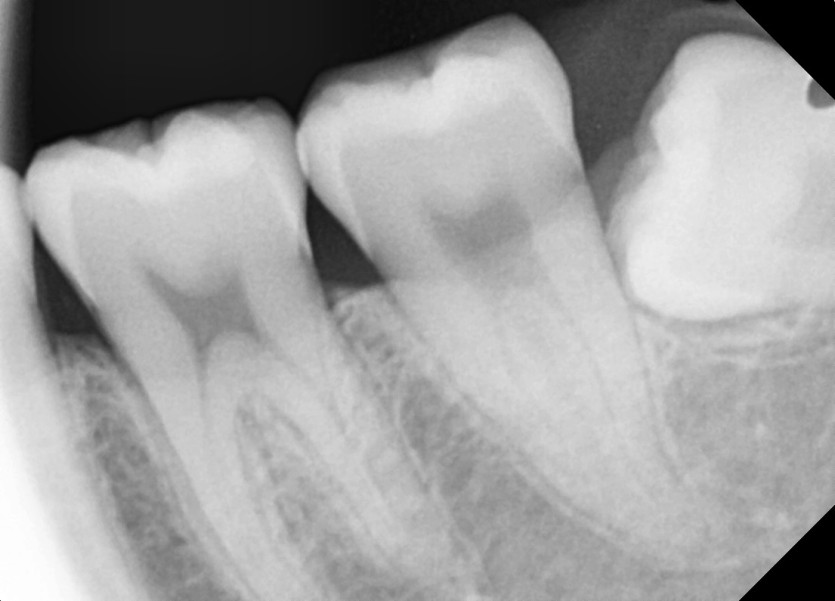

#28,38 사랑니 발치

구강 외과 전문의가 당일 발치했습니다.